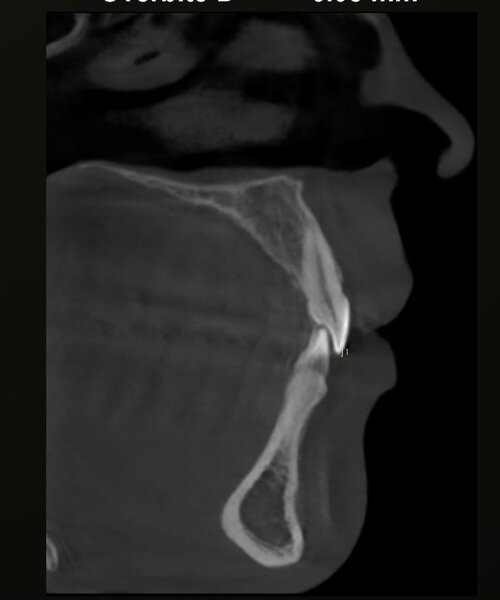

i have compressed airway (84mm smallest width), but doctors said i don't need surgery because i dont have sleep apnea.

also, they don't want to expand my palate because they said its only a little bit narrow so no worth the risk (upper palate 38.5mm, lower palate 42mm).

they want to extract my wisdom teeth to create space, and they said my overbite is gonna get fixed when they align my upper teeth, because they are blocking my lower jaw (my upper teeth grew inwards).